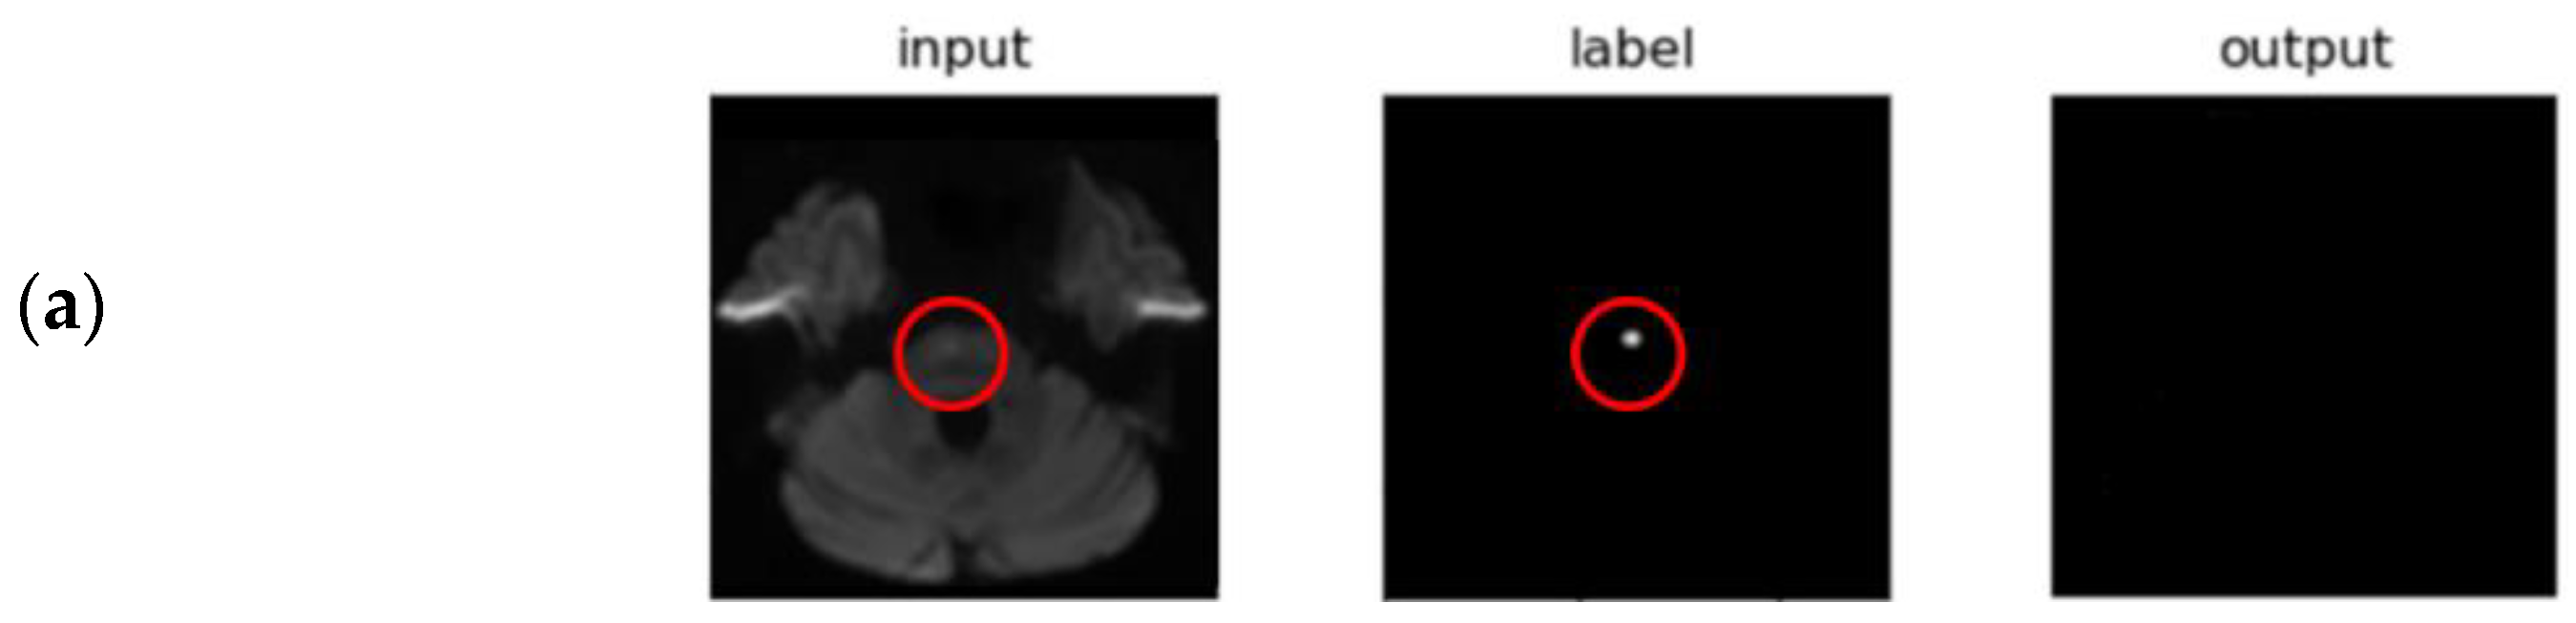

3.2. Segmentation Performance